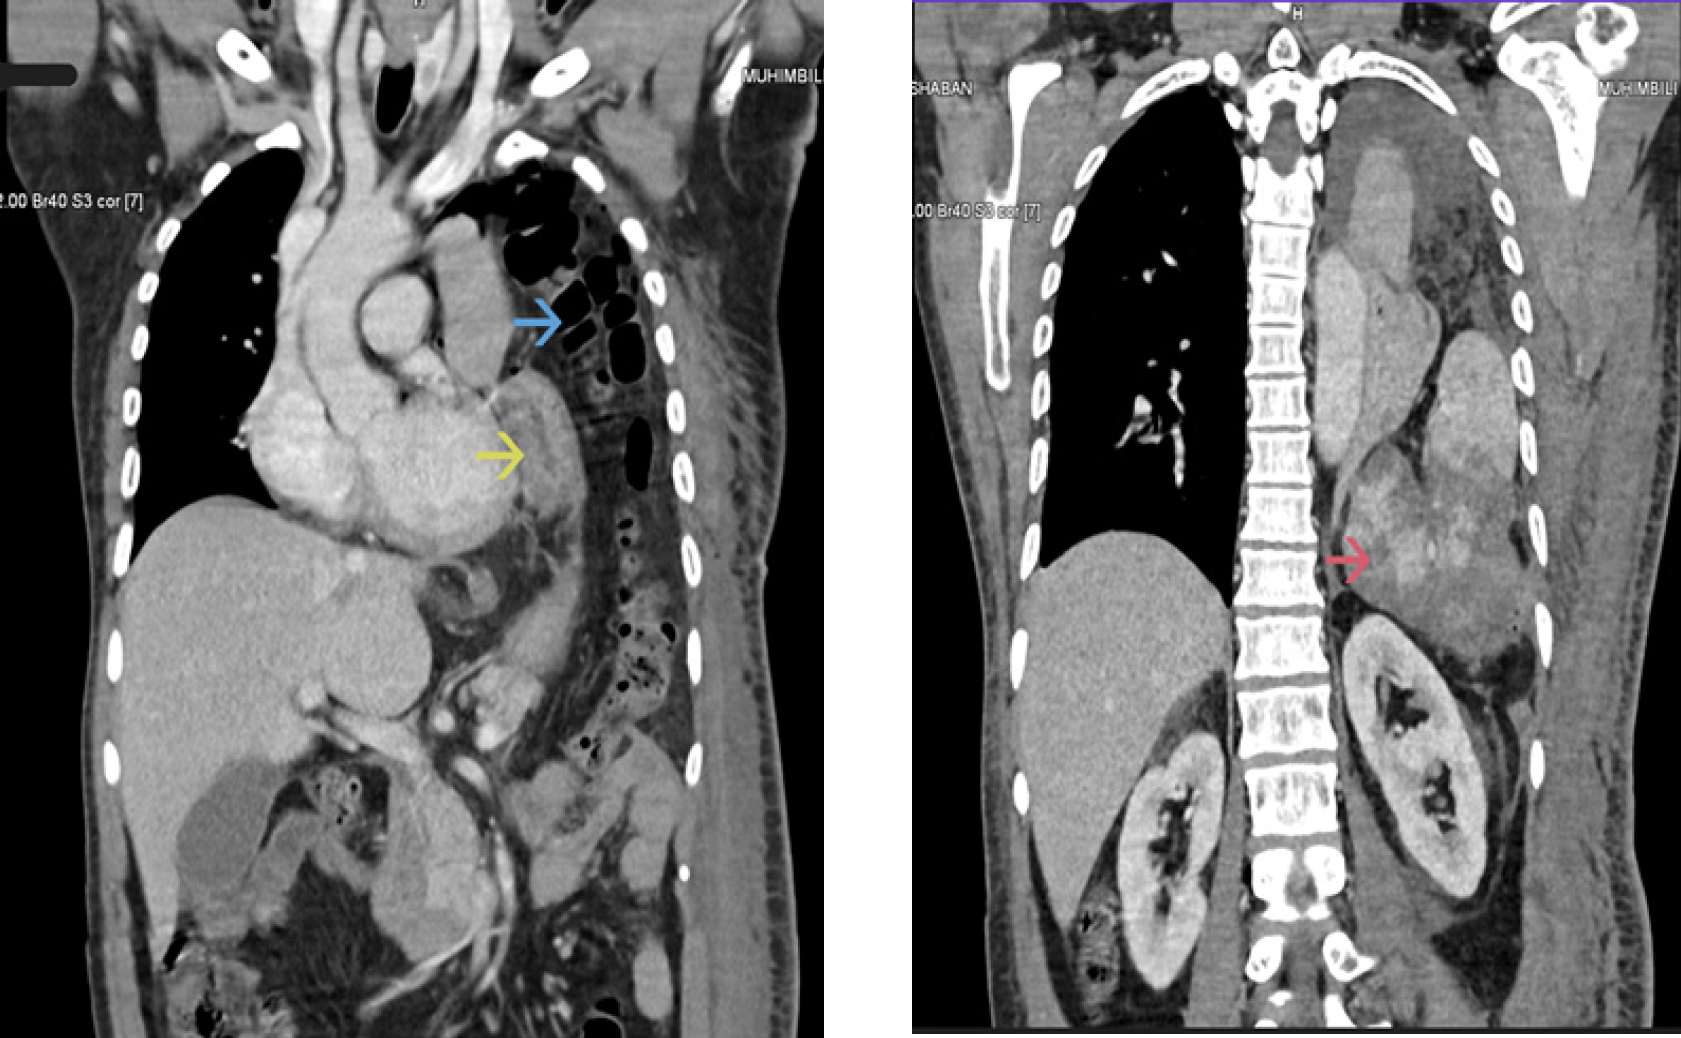

Case: A 55-year-old male involved in a motor vehicle accident presented to our facility hemodynamically stable, seven days after initial management for a traumatic hemothorax, with a missed diagnosis of diaphragmatic rupture and herniated, shattered spleen. The diagnosis was confirmed following a thorough physical examination and cross-sectional imaging. Laparotomy was conducted to perform a splenectomy and repair a diaphragmatic rupture, and the patient had an uneventful postoperative recovery.

Conclusion: This case highlights the critical need for a high index of suspicion and comprehensive evaluation in cases of high-energy trauma, emphasizing the importance of detailed examination and cross-sectional imaging in detecting overlooked injuries. The patient’s hemodynamic stability, despite a shattered spleen, may have resulted from the compressive effect of the hernia defect on the splenic vessels, a factor that could play a role in similar trauma cases.